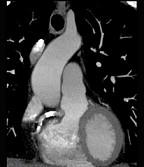

下面一组图像应考虑为 ( )A、左前降支钙化B、左旋支钙化C、正常的左前降支D、右侧冠状动脉钙化E、正常的右侧冠状动脉